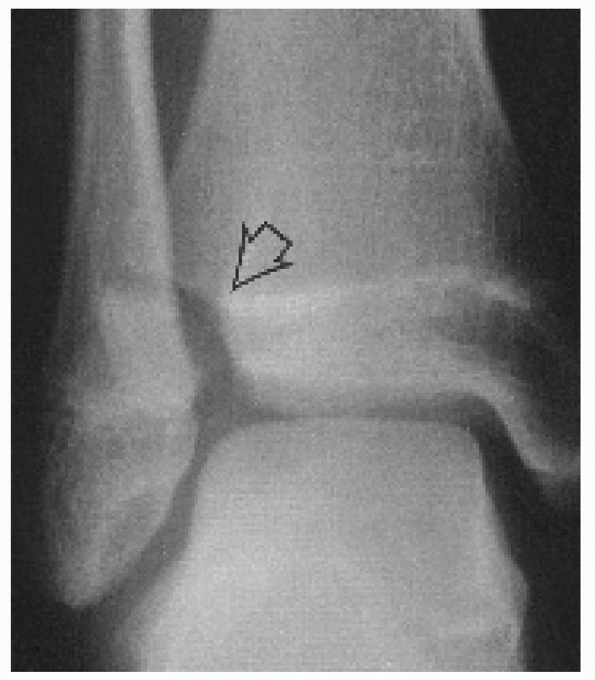

![]() |

FIGURE 26-21 Coronal and sagittal CT images of Tillaux fracture A. CT scan sagittal image of juvenile Tillaux fracture. Note the degree of intra-articular displacement. B. CT scan coronal image of juvenile Tillaux fracture. C. CT scan can facilitate screw placement/orientation. D. Reduction with intraepiphyseal screws.

production of such images (Fig. 26-22). These images can assist with minimally

invasive approaches and the use of percutaneous reduction clamps and screws.